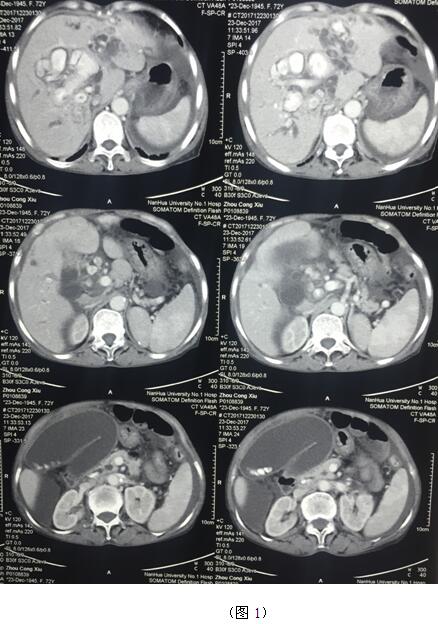

肝膽管結(jié)石疾病往往“鐘愛”貧困落后地區(qū)的病人,70多歲的周奶奶患全肝結(jié)石多年,由于家庭困難一直沒有得到有效治療,這個(gè)月病情惡化出現(xiàn)化膿性膽管炎并肝功能衰竭(圖1)。轉(zhuǎn)輾衡陽市內(nèi)多家醫(yī)院,不是因高昂的治療費(fèi)用止步于院外,就是被以“病入膏肓”為由推脫出院。家屬經(jīng)過多方打聽得知衡陽市中心醫(yī)院是市里面的仁濟(jì)醫(yī)院,肝膽外科還是省級重點(diǎn)???,家屬及病人懷著最后的希望來到了醫(yī)院肝膽外科。